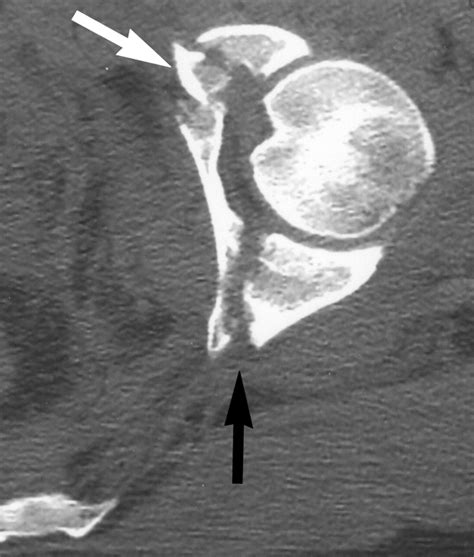

⚠️ Note: Surgical classification is highly specialized and requires high-resolution CT imaging with 3D reconstructions to accurately visualize the fracture fragments before planning surgery.

• CT Scans: The gold standard. A CT scan provides a detailed view of the articular surface and the displacement of fracture fragments.